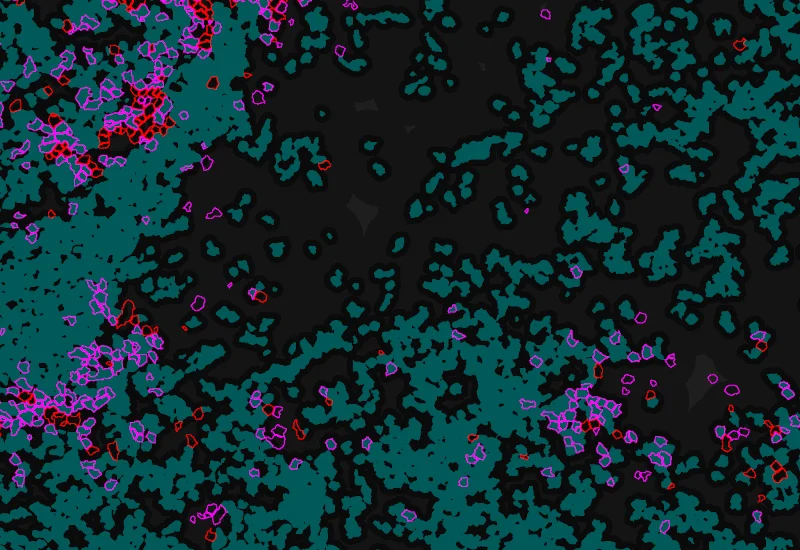

Phenotype 1 to 2 direct contact